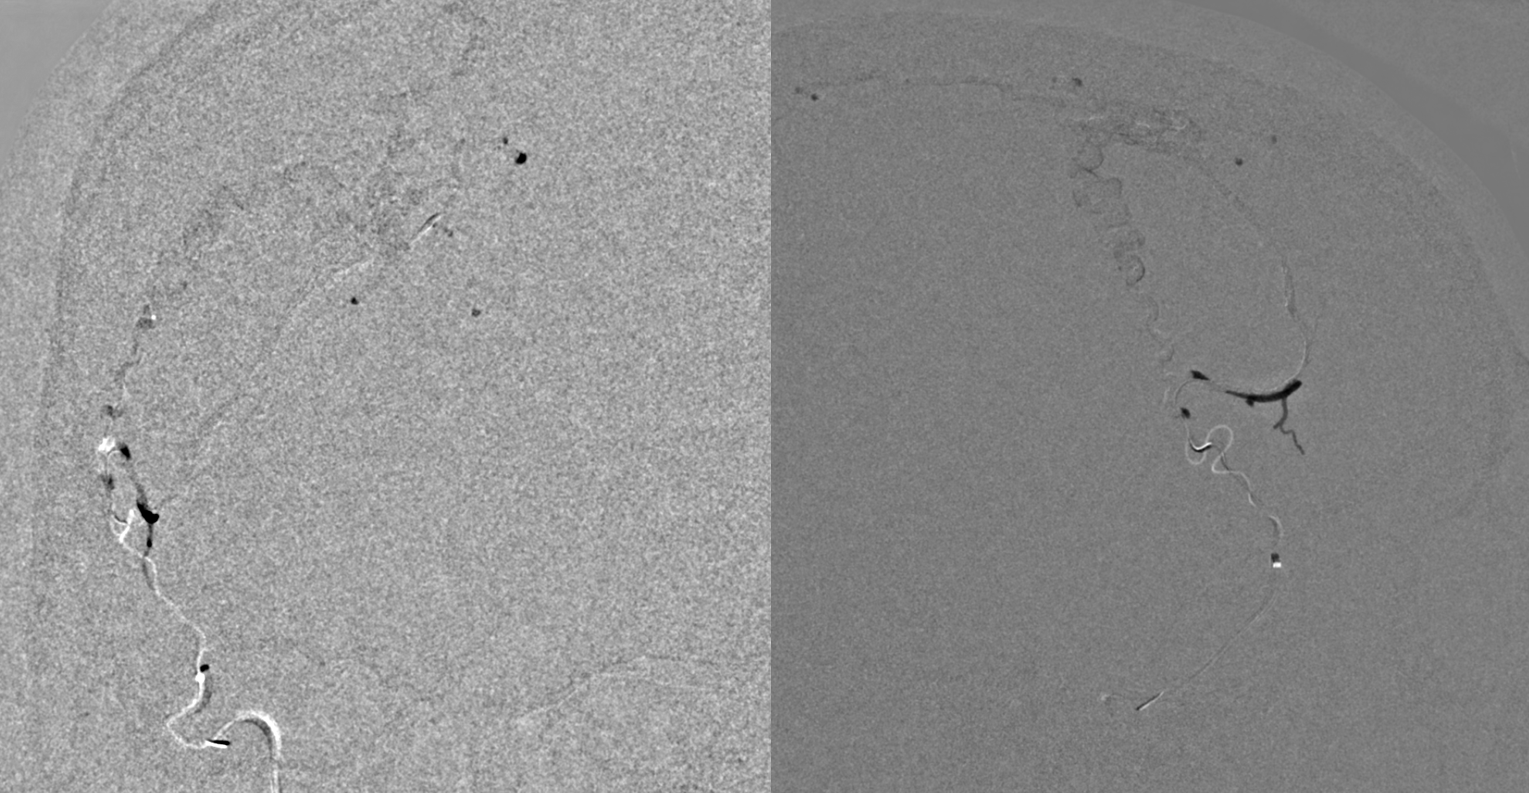

Angio — the good side

Bad side

Some venous CBCT etc